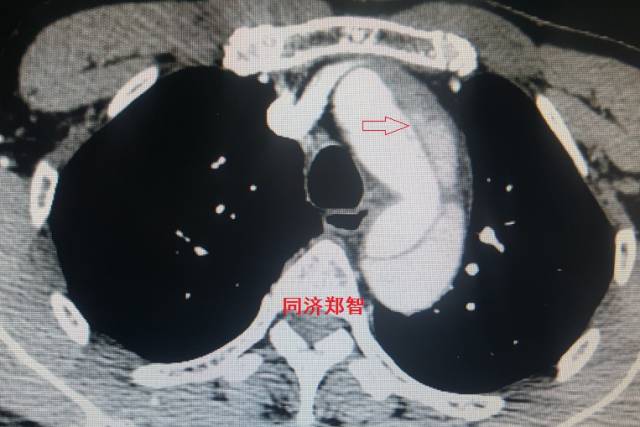

病例十

腹主动脉平扫CT提示正常外周一圈的钙化影中有内移的钙化影(红色箭头所示),CTA 证实为腹主动脉夹层。